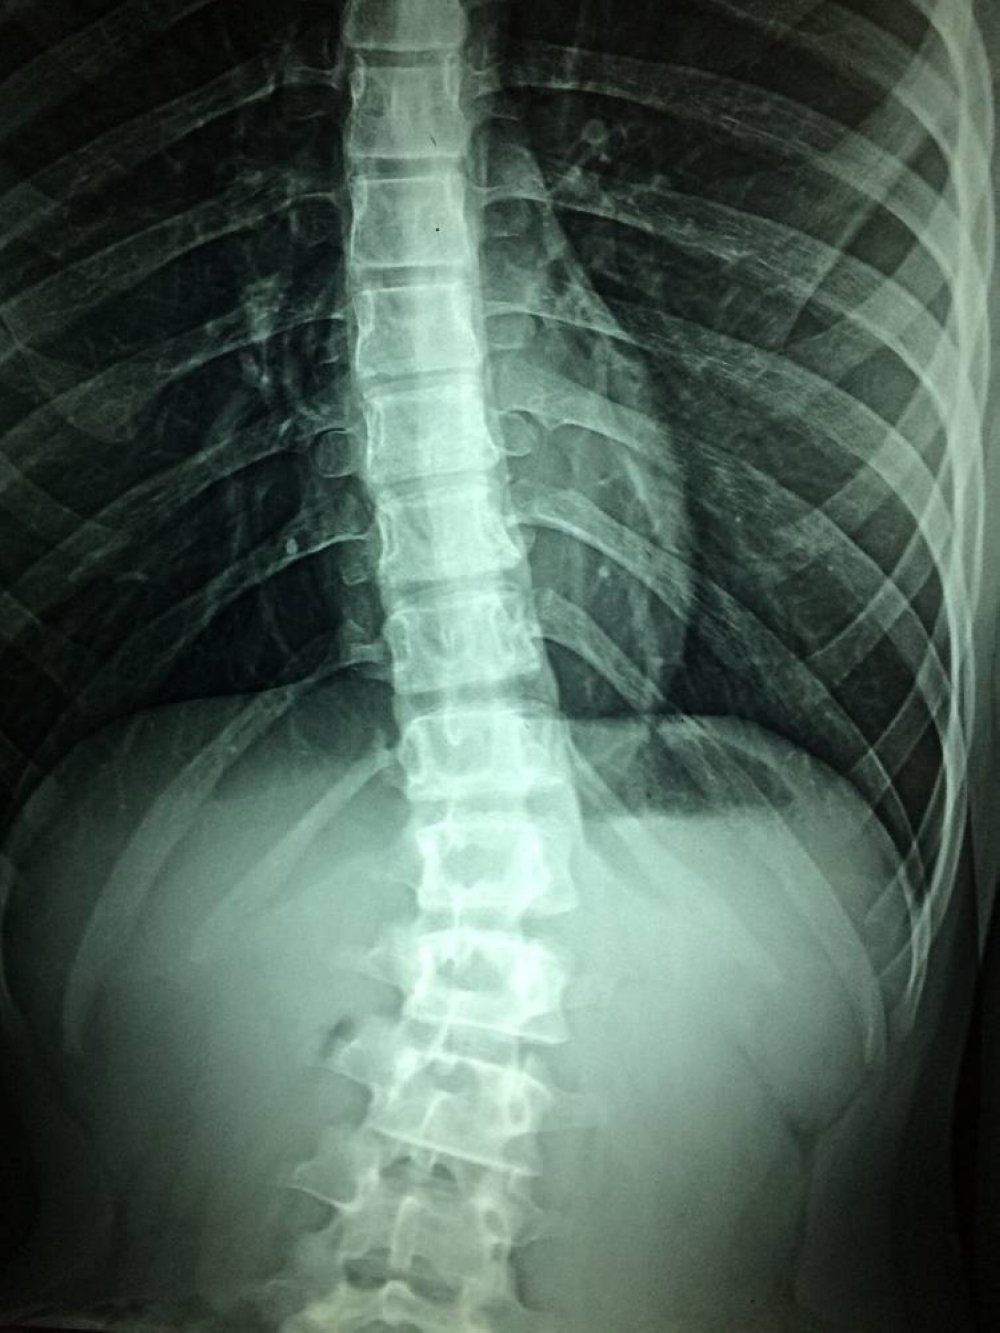

قال علماء يابانيون في جامعة «كيو» بطوكيو إن علاج الخلايا الجذعية ساعد في تحسين الوظيفة الحركية لدى اثنين من كل أربعة مرضى يعانون من إصابة في النخاع الشوكي في أول دراسة سريرية من نوعها.

ولا يوجد حتى الآن علاج فعال للشلل الناجم عن إصابات خطيرة في النخاع الشوكي، والذي يؤثر على أكثر من 150 ألف مريض في اليابان وحدها، مع 5000 حالة جديدة كل عام.